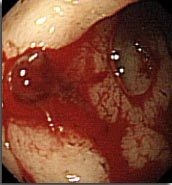

Q

Coloscopie pour bilan d’anémie ferriprive. qu’est ce que c’est?

A

tumeur colique